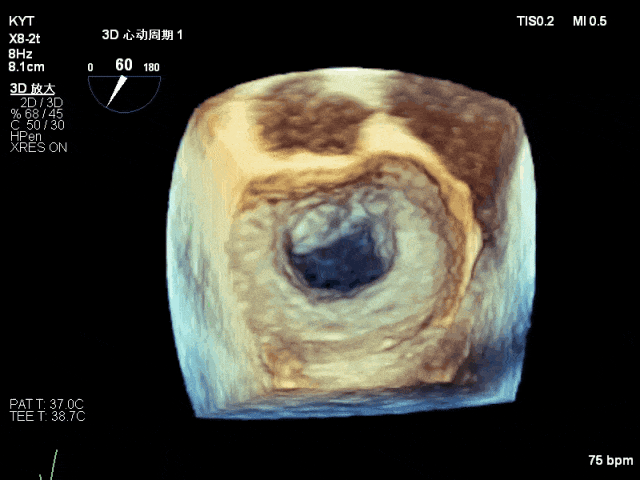

术前超声评估结果:

二尖瓣PC区收缩期脱向左房侧,其上可见飘带样回声。二尖瓣口左房侧见大量反流信号,主要呈偏心性并沿前叶走行达房顶并折返。

术前TTE及TEE影像:

TEE 3D示二尖瓣内交界区脱垂及断裂腱索